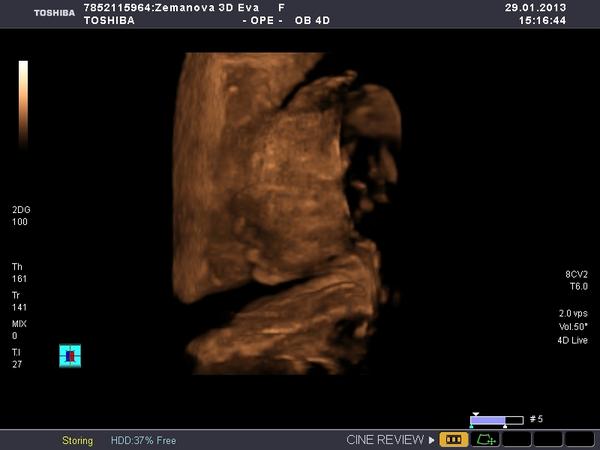

Ráno v 7:30 jsem opustila teplo svého domova a odjela sednout si k počítači a pracovat. Dosedla jsem v 8:10 a do teď u toho počítače dřepim (pár přestávek jsem měla, abych nekecala) a odhaduju, že ještě tak 2 hodiny tu dřepět budu a ráno v osm už mám zase vyzvedávat klienta a jet někam do horoucích pekel. A PAK MI NĚKDO VYSVĚTLETE, JAK TO NAŠI MYSLELI, KDYŽ ŘÍKALI,AŤ SE UČÍM, ABYCH MĚLA HEZKOU PRÁCI A MOHLA SI UŽÍVAT!?! jediný co mě s tím smiřuje, že můj hodný muž přijel a pomáhá mi, abychom to měli rychleji a má "prolhaná" matka je ve vedlejší kanceláři a dělá taky... Jestli se ve čtvrtek ukáže, že čekáme děvčátko, tak ho vychovám, aby se dobře vdalo a může být klidně úplně blbá.... 😀